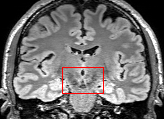

To test the impact of the iterative refinement on YODA’s translation quality, we compared regression and diffusion sampling on the RS data and present additional generation examples in Fig. 6. We observe that diffusion sampling visually resembles the appearance of the acquired images. Regression sampling preserves key anatomical features – the GM/WM boundary, WMHs (Fig. 4), the outline of the pallidum (Fig. 6) – but omits many high-frequency features. To investigate whether iterative refinement during diffusion sampling adds relevant and systematic medical information or only imitates acquisition noise, we performed ExpA sampling, i.e. averaging the output of several ( or ) diffusion trajectories. We observed a gradual loss of high-frequency details when increasing the (see also the supplementary video), indicating that the effect of the iterative refinement is non-systematic. For , the images are visually almost indistinguishable from the initial regression solution (see the supplementary video, and Fig.4 and 6). We directly compared the synthesis results of ExpA () and regression sampling quantitatively and found the differences to be minimal (SSIM: 99.73%, PSNR: 45.30 dB), i.e. diffusion sampling approaches the initial regression solution for a high . The quantitative analysis of the image quality (Tab. 1) showed that diffusion sampling impairs the assessed SSIM and PSNR in comparison to regression sampling for both the in- and external test sets, which we attribute to noise generation (Sec. 3.1). In turn, ExpA averages improved both metrics and, for , performed mostly on par with the regression solution in both test sets in terms of SSIM, while the PSNR in the RS was slightly increased (Tab. 1). However, we observed that ExpA sampling YODA improves the replication of systematic 3D low-frequency image intensity drifts (bias fields) due to the 3D synchronization in 2.5D diffusion sampling. Yet, this apparent advantage did not generalize to the external MBB dataset, as bias fields are MR protocol-specific.

To assess the suitability of YODA-generated images for WMH detection independent of segmentation tools, we also calculated the CNR (15) of WMHs. This confirmed that the contrast of WMHs is preserved in the regression images, whereas we noted slightly reduced WMH contrast for diffusion and ExpA-sampled images (Tab. 1).

We evaluated the impact of the proposed sampling methods on the performance of the independent, externally trained SHIVA-WMH tool as compared to manual reference labels (Tab. 1). Smoother images (higher or from regression sampling) yielded improved performance over those from diffusion sampling.

In comparison to acquired images, we noted a slightly lower Dice score (), but higher derived volume correlation (ALVR, ) for regression-sampling YODA

(Tab. 1).